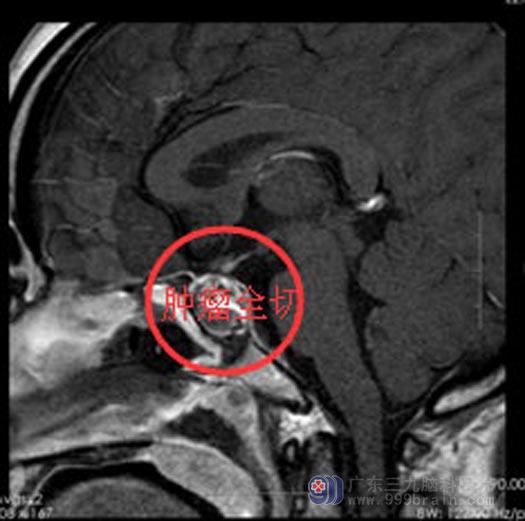

手术后